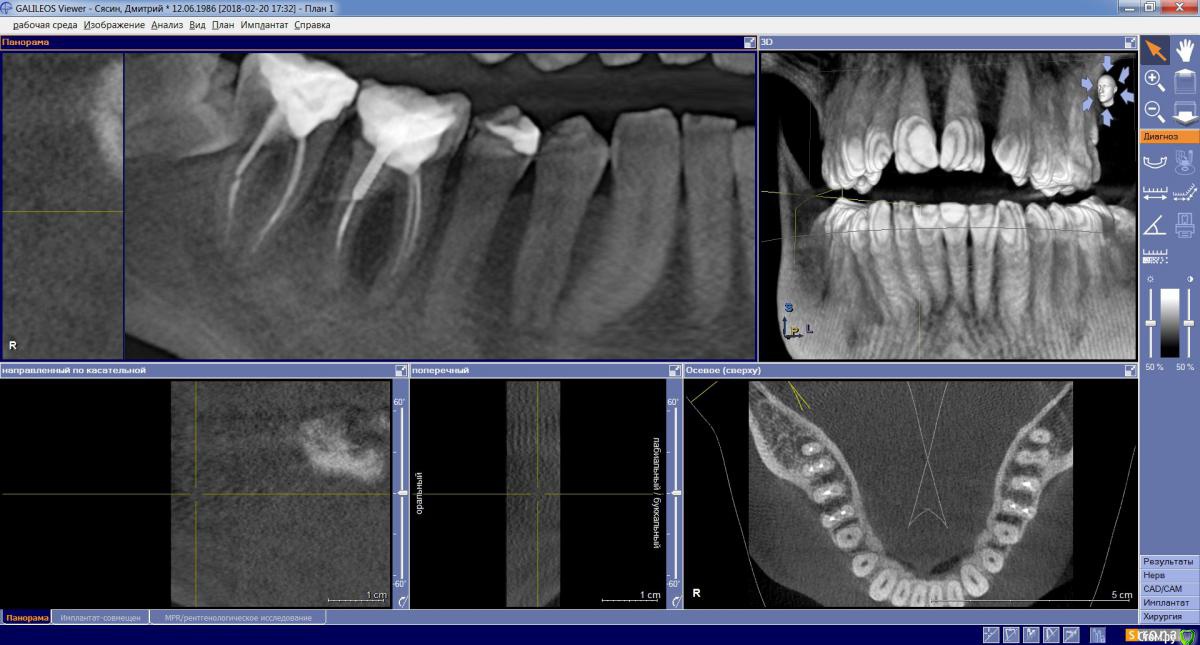

dims5 Опубликовано 21 февраля, 2018 Поделиться Опубликовано 21 февраля, 2018 Добрый день!Подскажите пожалуйста,если какая-либо надежда сохранить зубы 6-7? Зубы были пролечены несколько лет назад, не беспокоили длительное время и вот сейчас вылез свищ.Очень хочется сохранить зубы, а врач настаивает на удалении и постановке имплантов. Хотелось бы если есть хоть какая-то надежда попробовать из вылечить.Скриншоты сделал в разных нескольких разрезах чтобы лучше было видно состояние.Спасибо! Ссылка на комментарий

DmitrySH Опубликовано 21 февраля, 2018 Поделиться Опубликовано 21 февраля, 2018 Если судить только по снимку, то вполне нормальные шансы на сохранение зубов 6 и 7.А вот 8 надо убирать Ссылка на комментарий

St. Опубликовано 21 февраля, 2018 Поделиться Опубликовано 21 февраля, 2018 (изменено) +1 за лечение.Шансы есть, от Вас нужно время, терпение и найти доктора , плюс есть определенные финансовые риски( т.е. может быть так что старались, перелечили, но не помогло). Изменено 21 февраля, 2018 пользователем St. Ссылка на комментарий